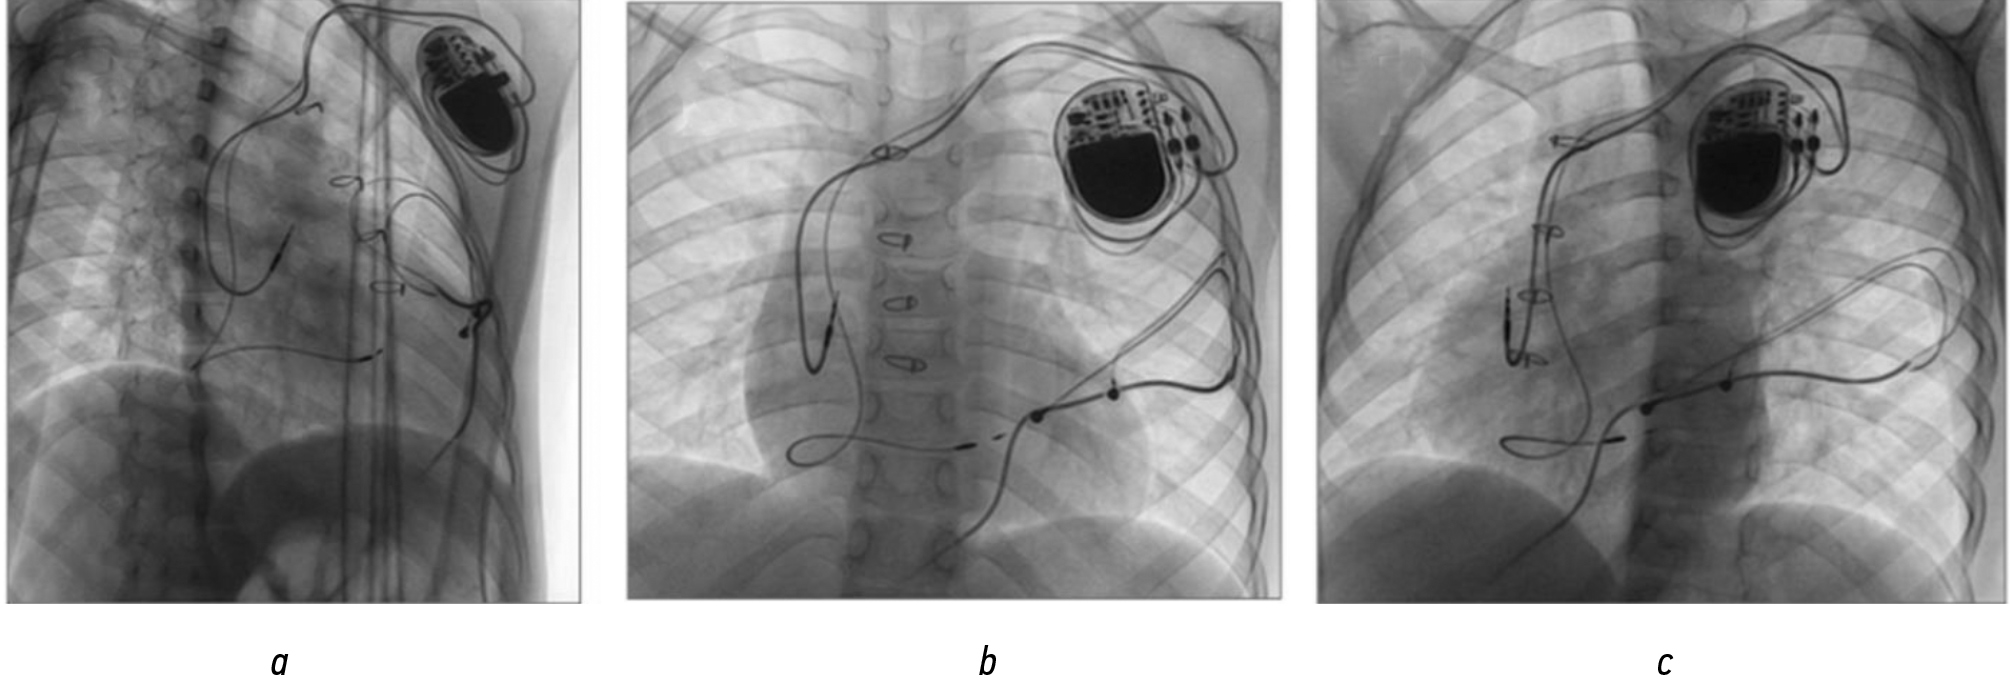

С помощью специализированной системы доставки, предназначенной для прицельной имплантации электрода в область пучка Гиса, «Select Site C315 His» (Medtronic, США) диаметром 2,4 мм (7Fr), бесстилетный электрод активной фиксации «Select Secure 3830» (Medtronic, США) длиной 59 см вкручен в межжелудочковую перегородку под контролем рентгеноскопии, электрического импеданса и морфологии стимулированных комплексов QRS. Импеданс в месте окончательной установки электрода составил 923 Ом; амплитуда зубца R — 9,6–11,3 мВ; порог стимуляции — 0,5 В при длительности импульса 0,40 мс. Ширина комплекса QRS в отведении V6 составила 134 мс; межпиковый интервал (RV1–RV6) — 52 мс; интервал St–RV6 — 52 мс. Предсердный электрод имплантирован в область ушка правого предсердия. По завершении вмешательства выполнена полипроекционная оценка положения электродов (рис. 2). ЭКС запрограммирован в режим работы DDD с базовой частотой стимуляции 70 уд/мин. Стимуляция ЛНПГ позволила добиться более физиологичного режима стимуляции с уменьшением ширины комплекса QRS c 152 мс до 136 мс (см. рис. 1, b).

Рис. 2. Рентгенография грудной клетки после имплантации эндокардиальной двухкамерной системы электрокардиостимуляции с желудочковым электродом в левой ножке пучка Гиса: a — правая косая проекция; b — прямая проекция; c — левая косая проекция.